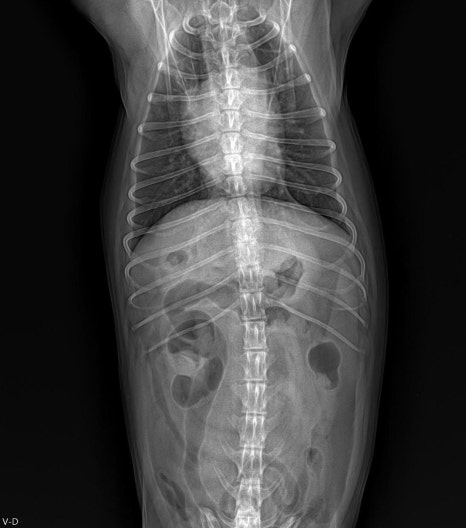

마취 전 혈액검사 및 방사선 검사를 통해 전신 상태와 수술 적합 여부를 확인했고 특이 이상 없이 안정적인 상태로 확인되었습니다.

수술 전 흉부방사선 검사 / 출처: 라온동물메디컬센터